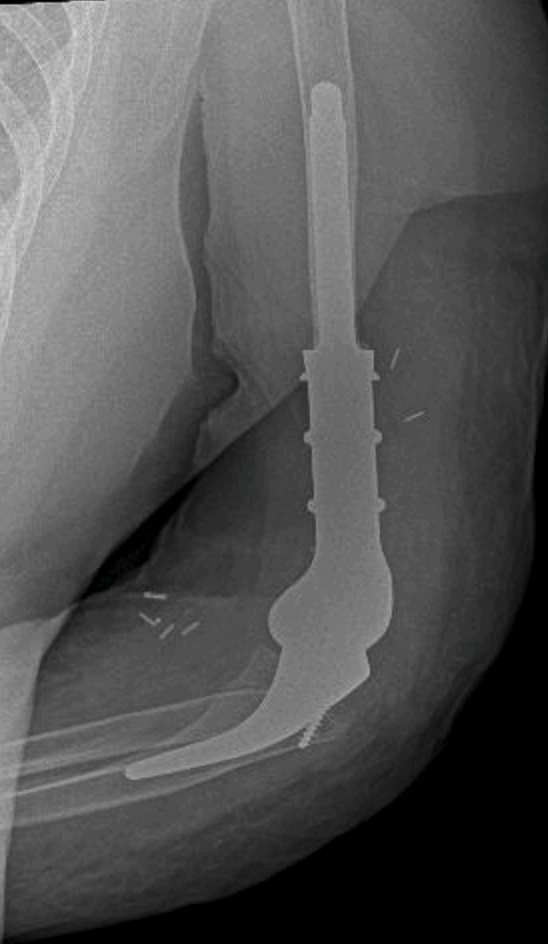

Fracturas del codo (húmero distal, cabeza radial, olécranon)

Artrosis de codo

Secuelas de traumatismos o cirugías previas